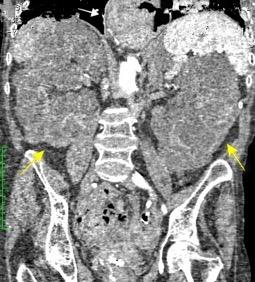

T. mixto de células germinales del testículo izquierdo

Nódulos pulmonares múltiples. (flechas verdes). Masas paratraqueales. (flechas amarillas). Dudoso ensanchamiento retrocrural (flechas negras). sigue….

Ttawfik A et al. Trans-diaphragmatic Pathologies: Anatomical Background and Spread of Disease on cross-sectional Imaging. Current Problems in Diagnostic Radiology. 2021.

T. mixto de células germinales del testículo

izquierdo Metástasis pulmonares. (flechas verdes). Ganglios paratraqueales. (flechas amarillas). Ganglios retroperitoneales (flechas negras)

Tawfik A et al. Trans-diaphragmatic Pathologies: Anatomical Background and Spread of Disease on cross-sectional Imaging. Current Problems in Diagnostic Radiology. 2021.